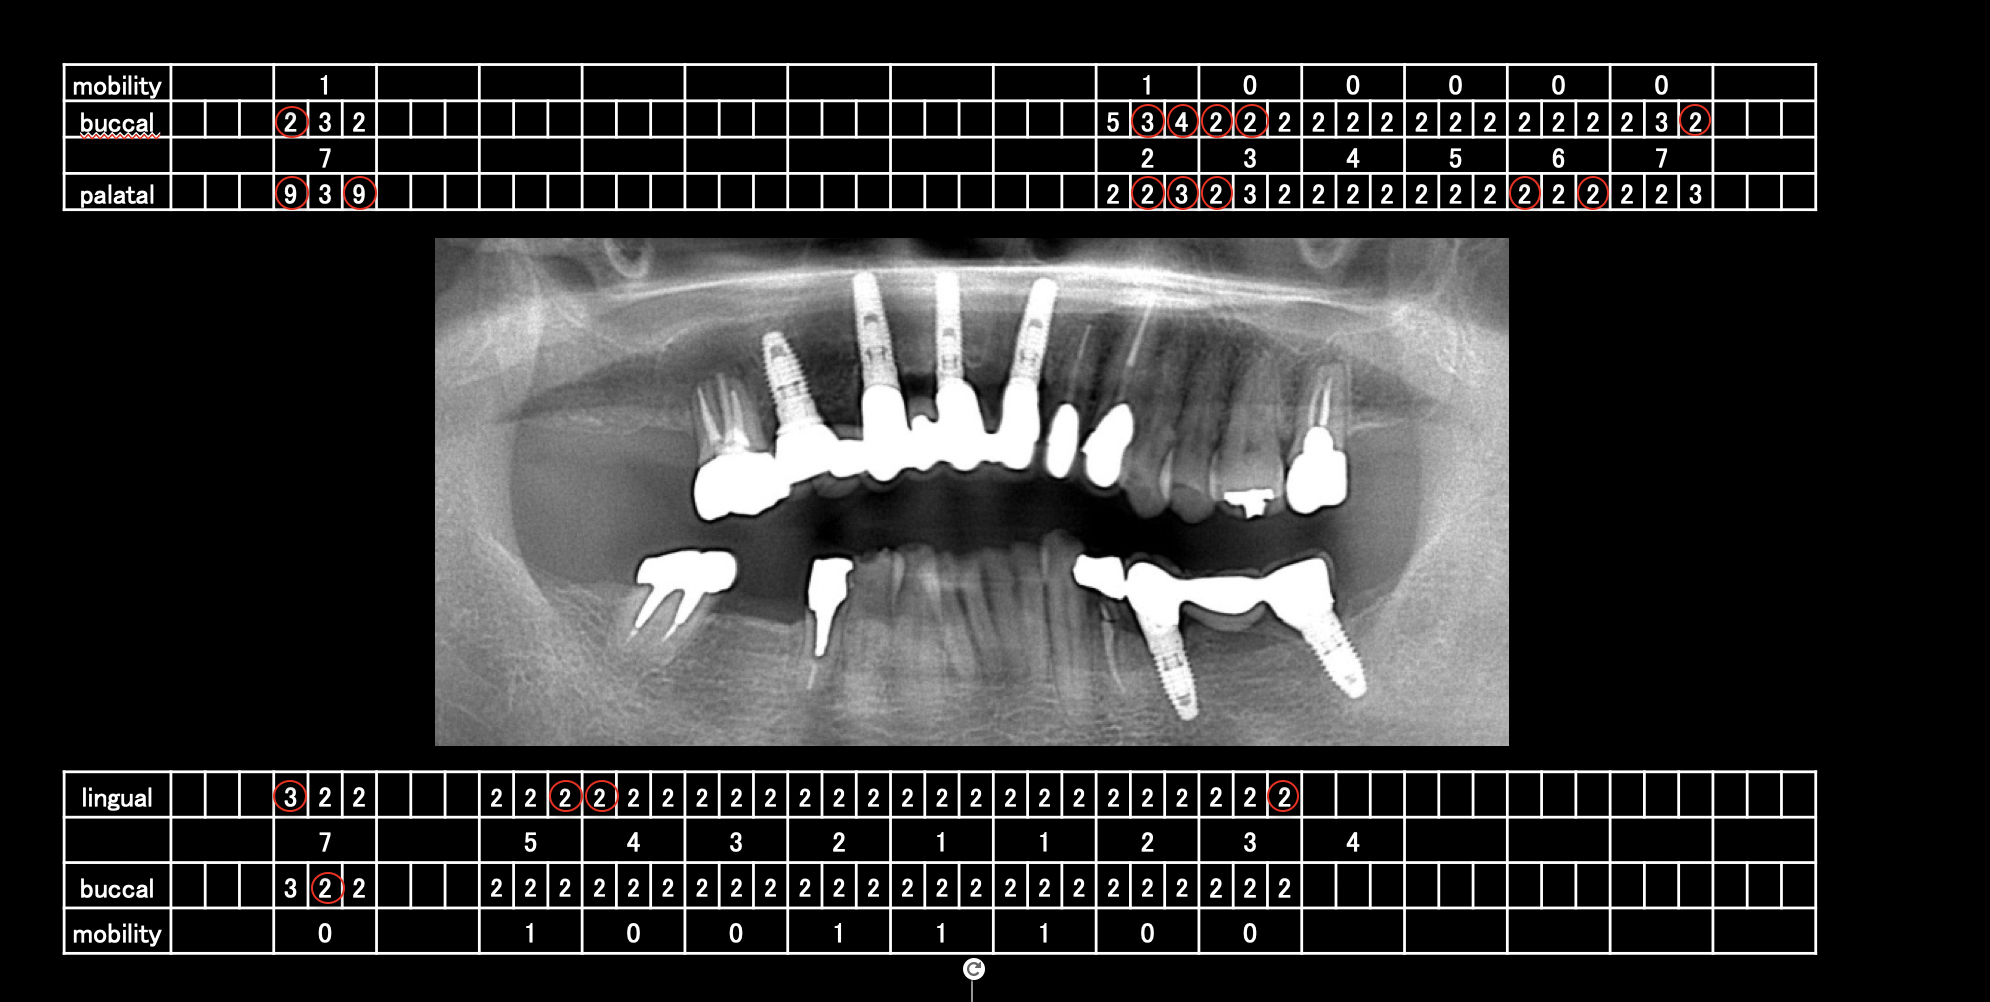

初診時検査結果

左上6番に深い歯周ポケットが認められます。根分岐部まで感染が広がっていたため、保存は難しい状況でした。